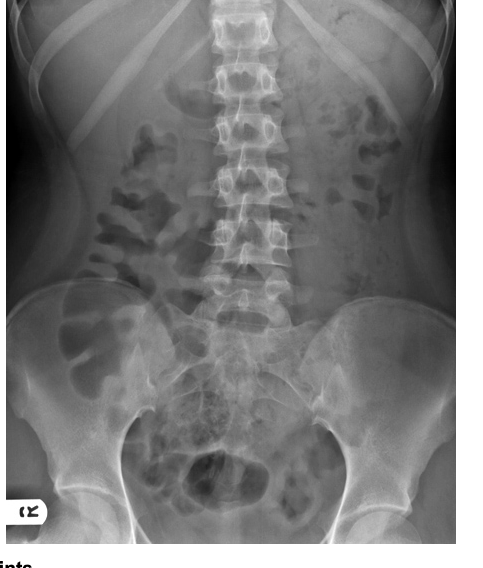

21

Q

24-year-old patient with suspected appendicitis. What does the image show?

Caecal volvulus

Normal appearances

Pneumoperitoneum

Small bowel obstruction

Toxic megacolon

A

Dilated loops of bowel with valvulae conniventes – lines crossing the full width of the bowel – indicates small bowel obstruction.

How well did you know this?